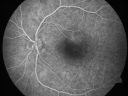

Serous Macular Detachment Left Eye - Possible Hypertensive Choroidopathy v. Central Serous Retinopathy691 views59-year-old woman decreasing vision in the left eye for about two days. She sees a spot in front of her vision. It is a yellow spot which is just straight ahead and moves with her eye. She does have high blood pressure. She checks her blood pressure at home, and even at home her blood pressure runs very high, with the systolic running around 200 and the diastolic around 100, although occasionally it does return to the normal range.

VISUAL ACUITY: Vision OD is 20/60, OS is 20/30Nov 30, 2010